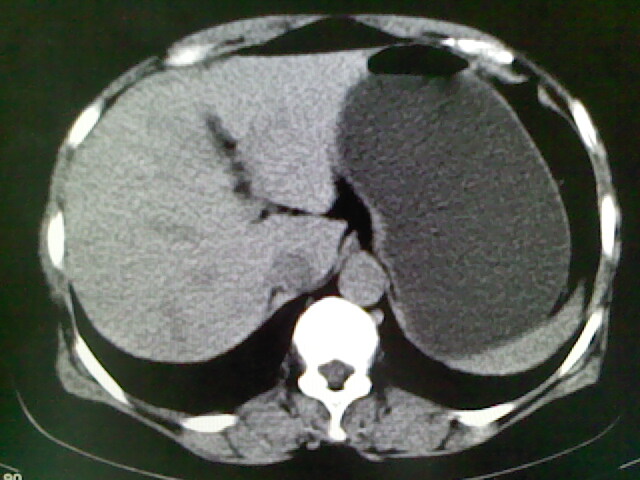

以下是引用卜一在2009-4-2 13:26:00的发言:[br]胆囊颈部结石伴胆囊炎!另:建议增强,待除外肝内占位及胆囊占位!

以下是引用liaoqiang在2009-4-2 16:23:00的发言:[br]胆囊是否切除?胆囊颈区致密影考虑金属夹?结石?肝脏右叶低密度影,考虑增强。